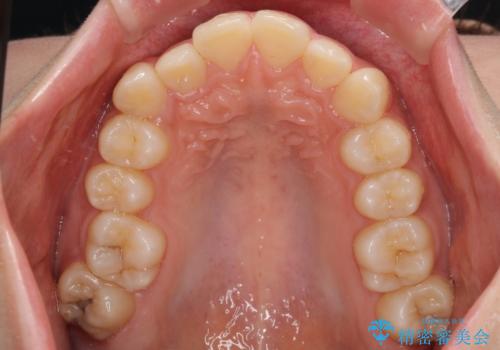

- 上顎前歯の突出感を気にして来院された患者様です。

上下左右第一小臼歯4本を抜歯して、積極的に口元を引っ込めるよう、ワイヤー装置にて矯正治療を行うこととしました。

抜歯矯正により、下唇が前方に突出した感覚が大幅に改善されました。